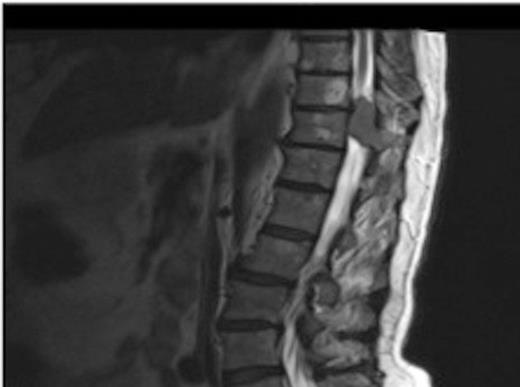

Original thoracic CT scan, which was performed 2 months prior to the MRI, shows the spinal metastasis

On review of the original thoracic CT scan, which was performed 2 months prior to the MRI, the tumour was distinguishable but, as the spine is such a rare location for carcinoid metastasis, it was initially unreported.